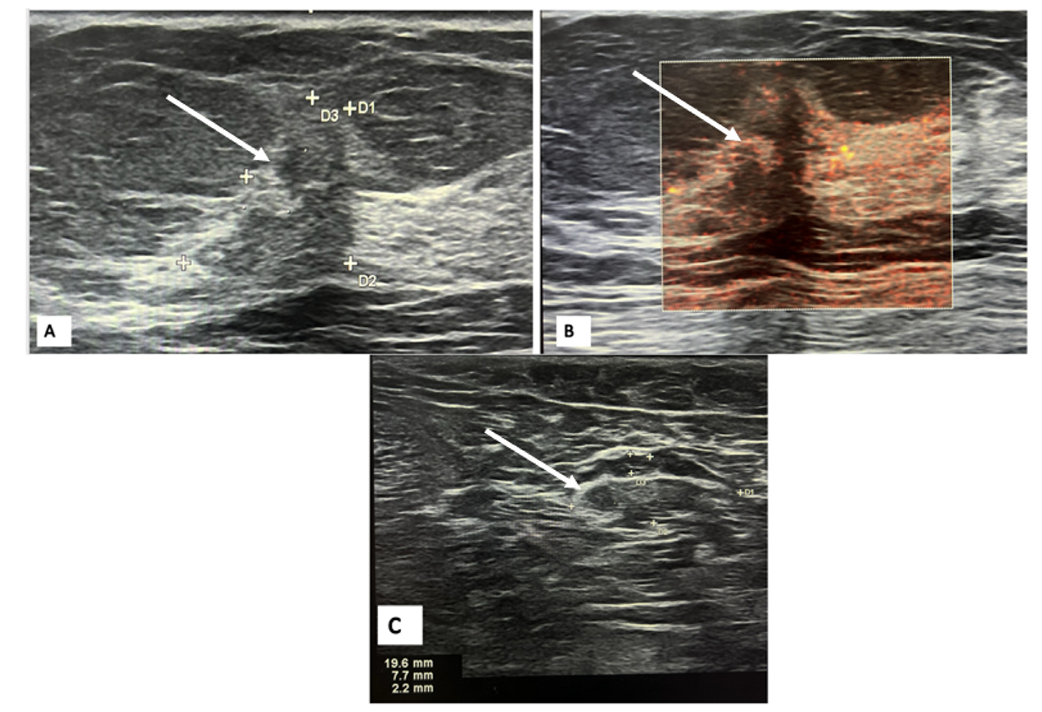

• 全身PET-CT检查显示胸腰椎和双侧髂骨有轻微的透亮区及轻度FDG摄取,未见明确溶骨性或成骨性高代谢病灶,乳腺及全身其他部位未发现提示原发肿瘤的高代谢灶。

图1 全身PET-CT